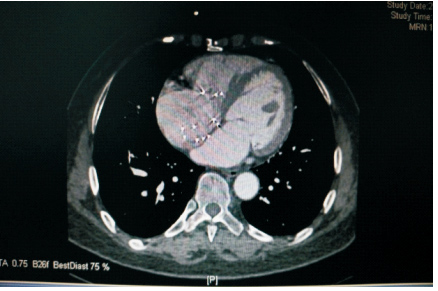

患者59岁,女性,因“发现心脏杂音3个月”于2011年1月份入院。患者2001年因下腔静脉狭窄于外院行下腔静脉支架植入术(支架厂家及型号不详),术后服用培达3个月后停药,无不适。2007年间断出现心悸及胸闷,未诊治。2011年单位体检发现心脏杂音,外院超声提示下腔静脉支架移位至右房,主动脉窦右房瘘。既往:体键。入院查体:血压120/70 mmHg(1 mmHg=0.133 kPa),心律齐,主动脉瓣第一听诊区可闻及Ⅲ/6级收缩期杂音,腹软,无压痛,双下肢不肿。入院诊断:下腔静脉狭窄,下腔静脉支架植入术后,下腔静脉支架移位,主动脉窦右房瘘。入院后相关检查:超声心动图:LV 53 mm,EF 74%,主动脉右冠窦与右房间探及破口约3~4 mm,下腔静脉入右房口处探及支架回声,支架突入右房约20 mm;胸片(图 1、2):侧位片金属支架结构影不连续,心影区偏前区可见线状高密度影。CT(图 3、4):右室游离壁、间隔壁、三尖瓣口、右房、下腔静脉近心段可见支架金属丝影。冠状动脉造影检查(图 5、6):冠状动脉未见明显异常,可见支架影随着心脏的跳动位置发生变化。